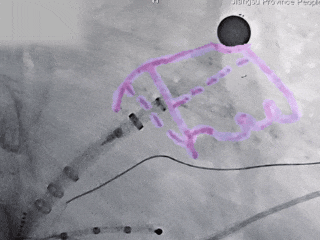

MemoLefort封堵器展开后DSA下造影评估

边造影边半回收,调整位置后重新退鞘,确保轴向,减少露肩

封堵器锚定位置良好

Lefort封堵器评估符合PASS原则,释放封堵器,封堵器位置稳定且未见残余漏

术前结合CT以及术中造影评估左心耳开口23.27mm,深度22.45mm,心耳内部空间较大,且患者全身情况良好,可较配合局部麻醉手术,采用极简式封堵术安全可行。术中考虑心耳开口和深度充足,可利用心耳空间进行退鞘释放封堵器,使封堵器完全封堵左心耳。术中采用半回收方式调整封堵器在心耳内的位置形态,确保封堵器放置位置合适,且牵拉稳固,术后封堵器形态完整,未见残余漏。本病例展开后即刻造影,平口封堵,上下缘不留残腔。封堵器压缩比为10%,压缩合适,术中符合PASS原则,释放封堵器,术后封堵器稳固锚定在心耳壁,封堵器与心耳紧密贴合,无过度扩张风险,显著提升封堵完整性。